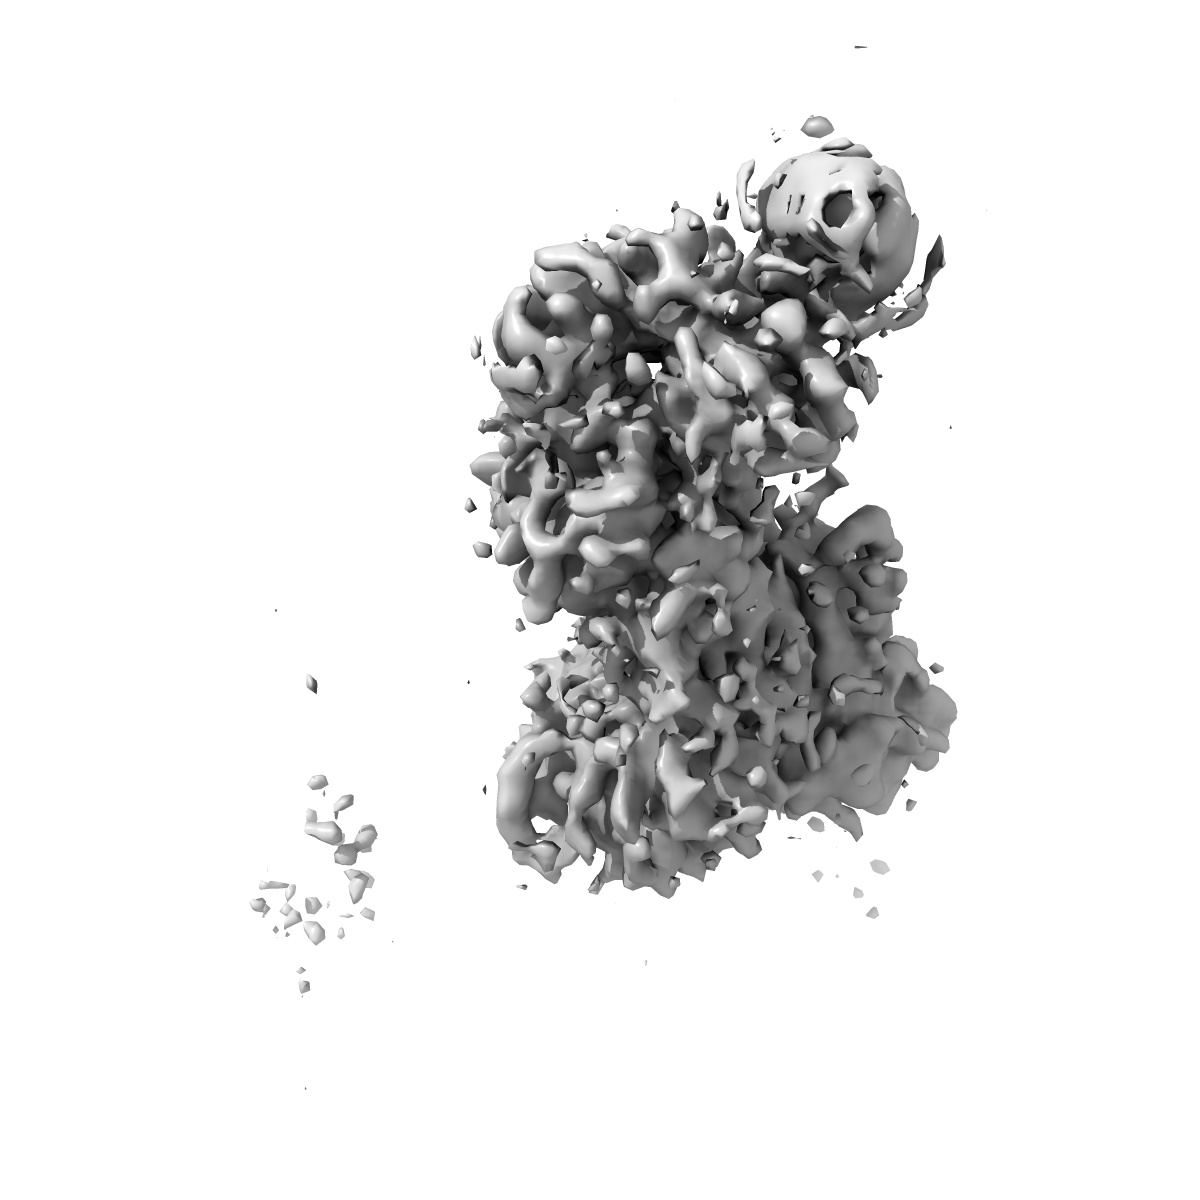

Structure of RBD directed antibody DH1042 in complex with SARS-CoV-2 spike: Local refinement of RBD-Fab interface

Single-particle3.87 Å

Fitted models: 7the